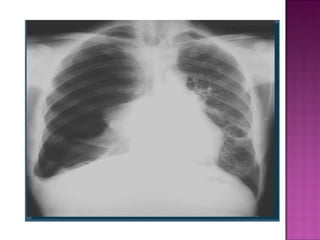

Los problemas que podemos encontrar en la cavidad pleural derivados de estas situaciones son: Neumotórax (aire en la cavidad pleural).  Hemotórax (sangre en la cavidad pleural).  Hidroneumotórax (líquido y aire en la cavidad pleural).  Derrame pleural (presencia de líquido en cavidad pleural). Pio tórax o empiema (presencia de pus en el espacio pleural).

Los problemas quepodemos encontrar en la cavidad pleural derivados de estas situaciones son: Neumotórax (aire en la cavidad pleural). Hemotórax (sangre en la cavidad pleural). Hidroneumotórax (líquido y aire en la cavidad pleural). Derrame pleural (presencia de líquido en cavidad pleural). Pio tórax o empiema (presencia de pus en el espacio pleural).